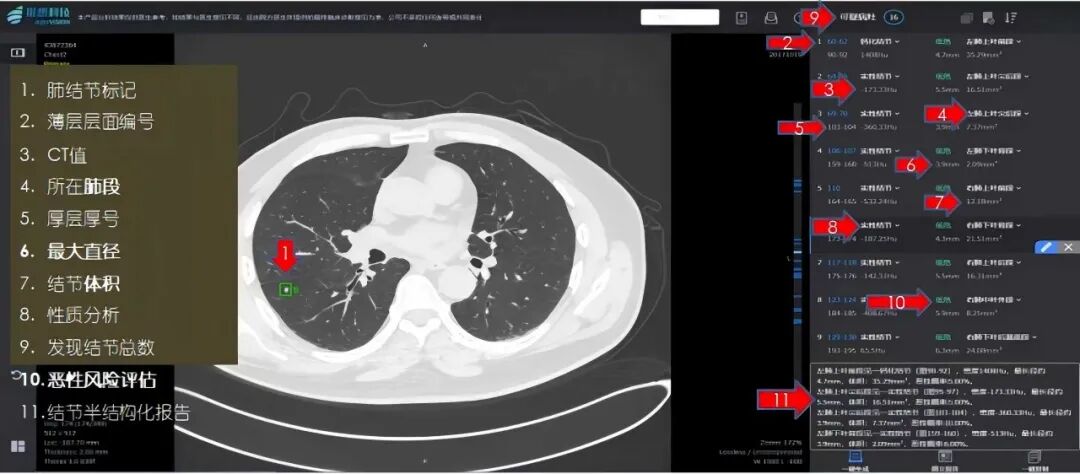

武汉红十字会医院引入肺结节人工智能辅助诊断系统以来,通过AI对CT图像进行“地毯式”筛查,有效减少因经验差异和视觉疲劳导致的漏诊。该系统能以像素级精度检测病灶并生成结构化报告,呼吸内科、胸外科、放射科等多学科专家综合结节特征、病史与生活习惯等因素,为患者制定个性化治疗方案,显著提升诊疗效率与精准性,让患者“少跑腿、看好病”,全面优化就医体验。

肺结节人工智能辅助诊断系统生成结构化报告